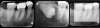

There are two specific types of DIDR sensor systems available to dentists in the marketplace: the hard-wired (HW) sensor and the photostimulable phosphor (PSP) sensor,1,2 also commonly known as phosphor "plates." A desirable feature common to both modalities is the ability to expose either bitewing (BW) or PA radiographic images. The BW radiograph (Figure 1) is usually considered more appropriate for caries detection, whereas the PA (Figure 2) is diagnostic for several different anatomic and pathologic issues.7

Fig 1. Left: Representative PSP BW radiograph with multiple restorative materials of varying radiographic densities. Tooth No. 31 demonstrates deep

caries on mesial aspect beneath the restorative. Radiolucency of carious lesion results from the low relative density of caries compared with healthy

tooth structure. Right: PSP BW radiograph optimized for view of multiple interproximal carious lesions.

Figure 1